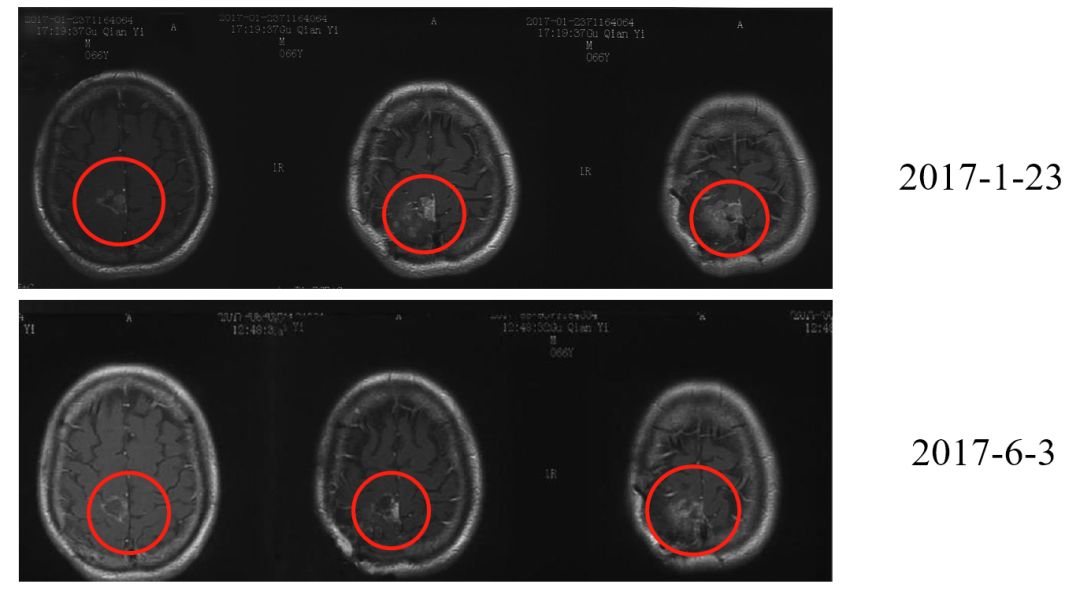

三次手术、靶向治疗并没有驱赶走病魔,患者病情逐渐恶化。2017年1月23日,其脑内右侧顶叶检测出一个大小为3.2×2.8cm的肿块,同时脑膜多发转移。

颅内多发病灶,2017年2月15日,在医生的权衡之下,患者开始尝试头部放疗联合靶向药安维汀治疗。2月15日至3月13日,共进行17次放疗。

2017年4月11日至2017年9月22日,患者先后接受4次CAR-T细胞回输。在第二次治疗后的胸部CT显示,原先充满肿瘤的肺部,现仅有右肺上叶有微小结节。

同时,9月18日的CT显示,患者已达到临床医学上的疾病稳定状态(SD,Stable Disease)。与5月26日的片子结果相仿,经四个多月的治疗,不断恶化的肿瘤终于得到了控制,无进展生存。